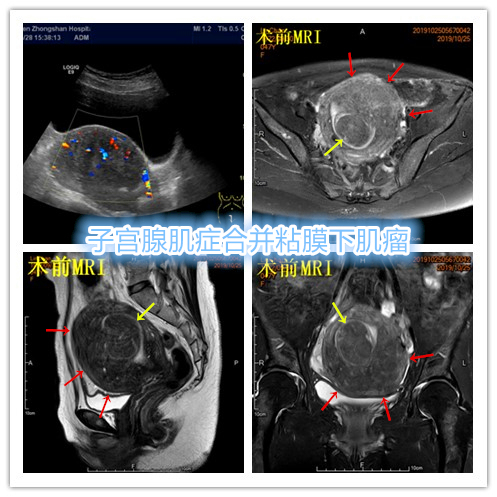

- 术前彩超、磁共振检查显示子宫明显增大,子宫前壁可见弥漫型子宫腺肌症病灶,合并粘膜下、肌壁间子宫肌瘤。

横断位

冠状位

矢状位